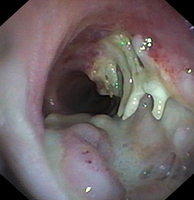

Deposition of fibrin